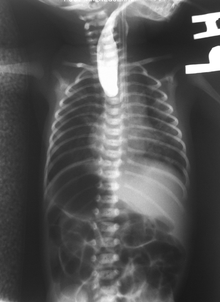

Common anatomical types of esophageal atresia a) Esophageal atresia with distal tracheoesophageal fistula (86%), Gross C. b) Isolated esophageal atresia without tracheoesophageal fistula (7%), Gross A. c) H-type tracheoesophageal fistula (4%), Gross E.[1] | |